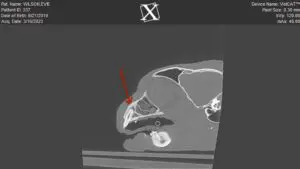

Above is a Cone Beam CT of a canine tooth of a cat that has a tooth root abscess. The tooth looked grossly normal. If you have ever had a tooth abscess, you want someone to put you out of your misery. Without anesthetizing this kitty and imaging the oral cavity, this poor pet would be suffering silently.